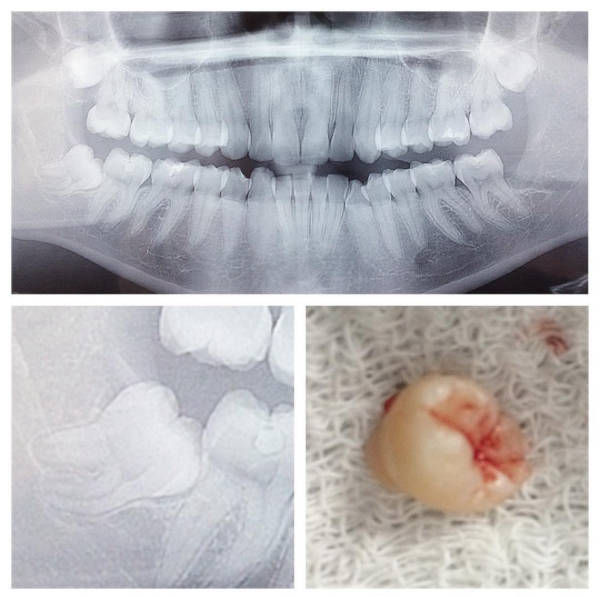

Vem de uma família tradicional de dentistas, iniciou sua carreira em clínicas da família, onde ganhou a prática em lidar com pessoas no seu dia a dia. Amante de cirurgia, fez residência em cirurgia oral menor no Hospital federal do Andaraí, e com o passar dos anos aprimorou seus conhecimentos através de cursos e congressos. Focada na área da estética, a Dra Juliana Audi Lima é especialista em Prótese Dentária e se dedica absolutamente em proporcionar uma melhor qualidade de vida e estética aos seus pacientes. Além de membro da Associação Brasileira de Odontologia, faz parte do seu corpo de professores desde 2017. Atua em Cirurgias, Implantes dentários, Prótese e Ortodontia

*Implante Dentário